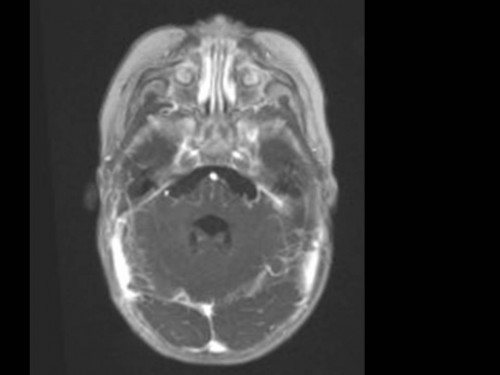

10 Monate altes Mädchen. Der Kinderarzt stellt fest, dass das kleine Mädchen einen recht großen Kopfumfang hat, nicht mit den Augen fixiert und anscheinend auch nicht richtig sehen kann. Damit bestätigt er die größten Befürchtungen der Eltern, denen in den letzten Wochen aufgefallen war, dass ihre Tochter nach keinem Spielzeug mehr greift und sie nur dann anlächelt, wenn sie zu ihr sprechen.

Bildgebung - MRT